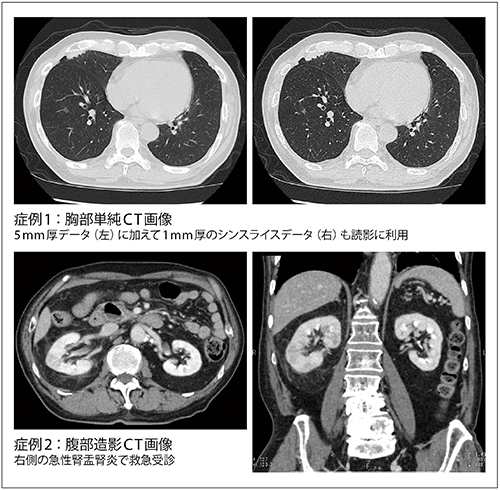

■Aquilion PRIMEによる臨床画像

1mmのシンスライスデータを読影にルーチンで活用

画像診断室では、CT画像についてはPACSに保存される5mm再構成の画像に加えて、1mm再構成画像をすべての症例で作成し3Dワークステーションに転送している。門澤センター長はシンスライスデータの活用について、「読影の際、必要に応じて技師にシンスライスデータの作成を依頼していると、どうしてもタイムラグが発生します。効率良く読影を進めるためには、このような運用が最善と考えています。再構成にかかる時間や手間、読影の負担もありますが、多列CTが本来持っている性能を生かすにはシンスライスデータから得られる再構成画像の活用が不可欠だというポリシーで読影しています。恥ずかしながら、この運用を開始して初めて脊椎圧迫骨折が高齢者に非常に多いことに気づかされました」と述べている。